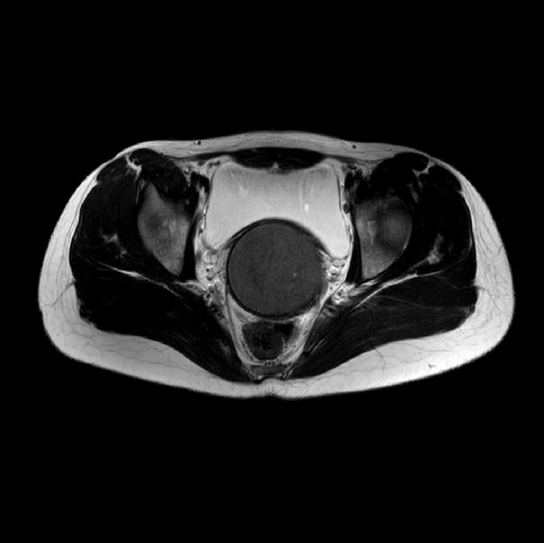

16岁花季少女,第二性征发育及营养状况良好,无躯体及头面部发育畸形,至今竟无月经来潮,完善经腹部超声提示盆腔探及囊性暗区71*68mm,逐步完善盆腔MRI及经直肠超声、专科检查,揭开了神秘的面纱。